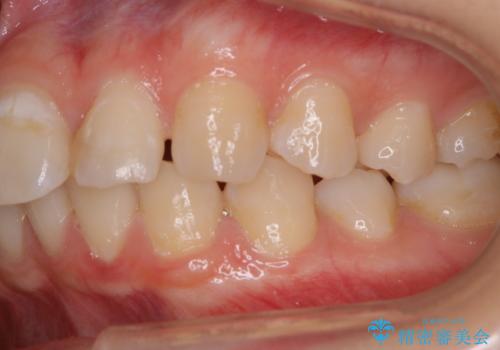

- これからインビザラインでのマウスピース矯正が始まるので、歯石取りをしてほしいとのことでした。

PMTC60分コースを行いました。

歯並が、がたついている場合はなおさら汚れが溜まりやすいです。矯正治療前や矯正中、定期的にPMTCをすることで、矯正治療中の歯肉トラブルを防ぐことにつながります。